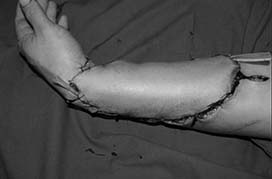

압궤손상 되어 거의 모습을 보이지 않을 정도의 하퇴부 모습.

골절부의 외고정 상태를 보여줌.

수술 후 피부가 괴사 된 외형 사진.

괴사 된 피부 절제 후 모습.